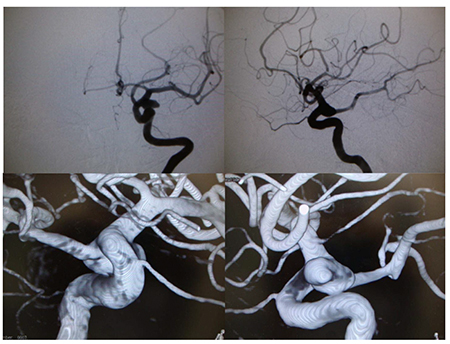

緊急脳血管撮影を施行し、左内頚動脈- 後 交通動脈分岐部動脈瘤を認めた。動脈瘤は ワイドネックでかつネックより後交通動脈 が分岐しており、密な塞栓を得ることは非 常に困難であると予想された。(図8)しか し高齢かつ意識昏睡の状態であるため、よ り侵襲の少ないコイル塞栓術を全身麻酔下に行った。

図8

図8 治療前左内頚動脈撮影

上段左:正面像 上段右:側画像

下段:3D-DSA